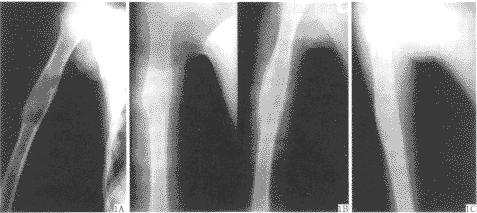

【摘要】 目的 介绍自体骨膜骨髓复合移植修复少儿良性骨肿瘤切除后骨缺损的方法。方法 抽取自体髂骨骨髓,自然形成凝块后植入骨缺损处,自体胫前骨膜切成1~2mm2 邮票状,均匀植入骨髓凝块中。 结果 随访4~10个月,术后1个月新生骨形成,术后3~4个月14例骨缺损处新生骨骨密度与周围骨组织一致,术后4个月恢复正常的关节功能和肢体负重功能。结论 自体游离骨膜骨髓复合移植 ......